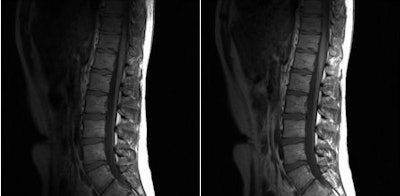

![]() |

| Images of the lumbar spine show reduced shading and improved C/N between a standard MRI (left) and multitransmit MRI (right) with T1-weighted imaging. All images courtesy of Christopher Filippi, MD. |